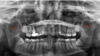

What does the red indicate in the following image?

Maxillary sinus

What does the yellow indicate in the following image?

Zygoma

Zygomatic process of the maxilla